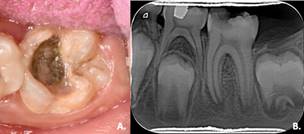

Al examen clínico, se observó encía levemente edematizada y eritematosa asociada al acúmulo de placa dentobacteriana. En el diente #36 (superficie vestibular y lingual) se detectó una opacidad demarcada de color amarillo asociada a una lesión atípica de caries dental activa y cavitada en la superficie oclusal (Figura 1A). A la prueba de sensibilidad pulpar de frío respondió de manera grave (+++) y persistente luego de retirar el estímulo; a la de percusión vertical de manera leve (++); y a las de movilidad y palpación de manera normal. En la radiografía periapical del diente #36

Figura 1 A. Aspecto clínico de primer molar inferior izquierdo permanente con HMI severa + lesión de caries activa y cavitada. Julio 2021.; B. Radiografía de primer molar inferior izquierdo permanente (36). Julio 2021.

se observó una imagen radiolúcida en la corona compatible con lesión de caries dental. En mesial presentaba imagen radiopaca compatible con material de restauración desadaptado. También se observóimagenradiolúcidaenlabifurcación compatible con proceso infeccioso y formación radicular incompleta (Figura 1B). Durante la consulta se observaron en la paciente actitudes de timidez, rechazo al tratamiento, bloqueo de la comunicación, aceptación de algunas órdenes y por momentos llanto monotónico. De acuerdo con los hallazgos clínicos y radiográficos se establecieron los siguientes diagnósticos: